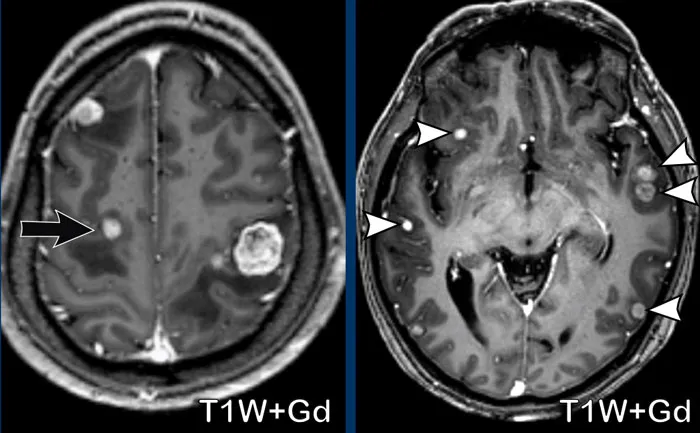

- Imaging reveals ring-enhancing lesions with significant vasogenic edema on contrast-enhanced CT/MRI.

ā While primary CNS tumors are typically solitary, the presence of multiple intraparenchymal lesions is the hallmark of metastasis.

- Hallmarks: Multiple, well-circumscribed lesions, typically at the gray-white matter junction.

- Appearance: Ring-enhancing lesions with significant vasogenic edema.

ā High-Yield Fact: Metastases often occur in arterial "watershed" areas, where blood vessels terminate, making it easier for tumor emboli to lodge and grow. This explains the characteristic location at the gray-white junction.